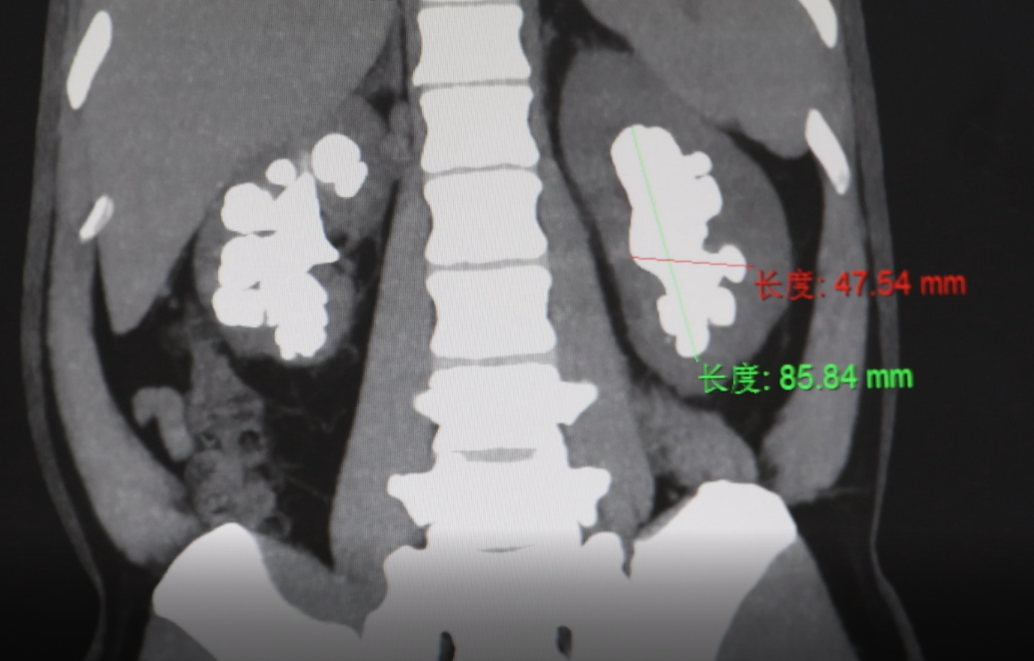

近日,贺州广济医院泌尿外科接诊一名患者,其双肾被结石完全填满,最长结石约9公分,而这一切的根源,竟是他对“无症状结石”长达十年的忽视。

“左侧的结石上下接近9公分,我们正常肾脏大小一般9.5到10公分左右,这个结石几乎把肾脏填满。” 贺州广济医院泌尿外科首席专家于永刚介绍,这种“安静型”结石潜在危害更大,切勿因无症状而放松警惕,可能导致双侧肾萎缩、感染,最终引发肾功能衰竭。

影像结果显示,患者左右双肾已被大小不等的结石密集占据,病情危急。由于结石体积大、数量多,手术难度较高,于永刚主任带领导团队经过充分评估,决定为其分两期实施取石手术。10月15日上午,于永刚主任与莫正周副主任历经2个多小时的奋战,成功将患者左肾内的结石彻底清除。